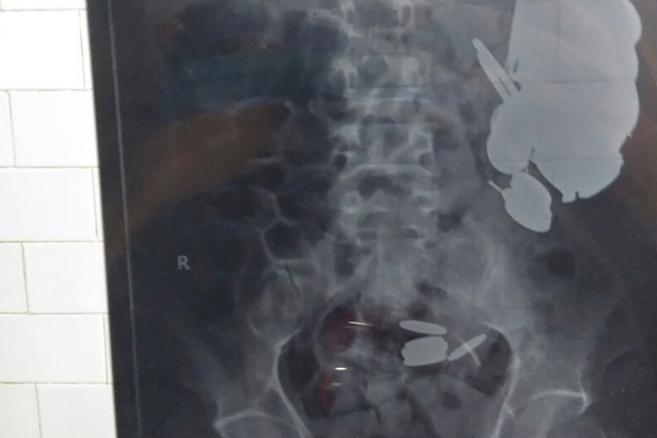

Cum se stabileşte diagnosticul?

”Atunci când nu există o traumă recentă, diagnosticul poate fi stabilit în urma examenului clinic fără a fi nevoie de alte investigaţii. Acest diagnostic poate fi unul ce ţine de patologia articulaţiilor sau una ce ţine de patologia tendoanelor” completează medicul.